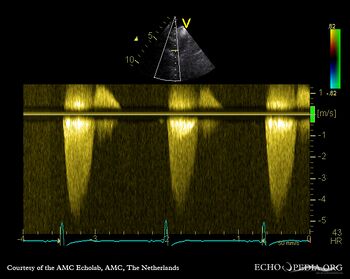

| Courtesy of: AMC Echolab, AMC, The Netherlands | |

| Continuous-wave signal of flow in arteria pulmonalis | PSAX with Color Doppler |